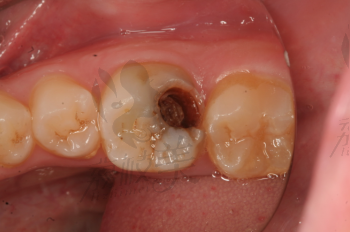

牙齒疼痛是常見(jiàn)的口腔問(wèn)題之一,而牙爛了個(gè)大窟窿晚上痛更是讓人難以忍受,這種情況不僅影響生活質(zhì)量,還可能引發(fā)其他口腔疾病,本文將為您解析牙爛窟窿的原因,并探討應(yīng)對(duì)方法和預(yù)防措施。

牙爛窟窿的原因

1、齲齒:齲齒是牙齒爛掉的主要原因之一,長(zhǎng)期不注意口腔衛(wèi)生,細(xì)菌滋生導(dǎo)致牙齒逐漸腐蝕。